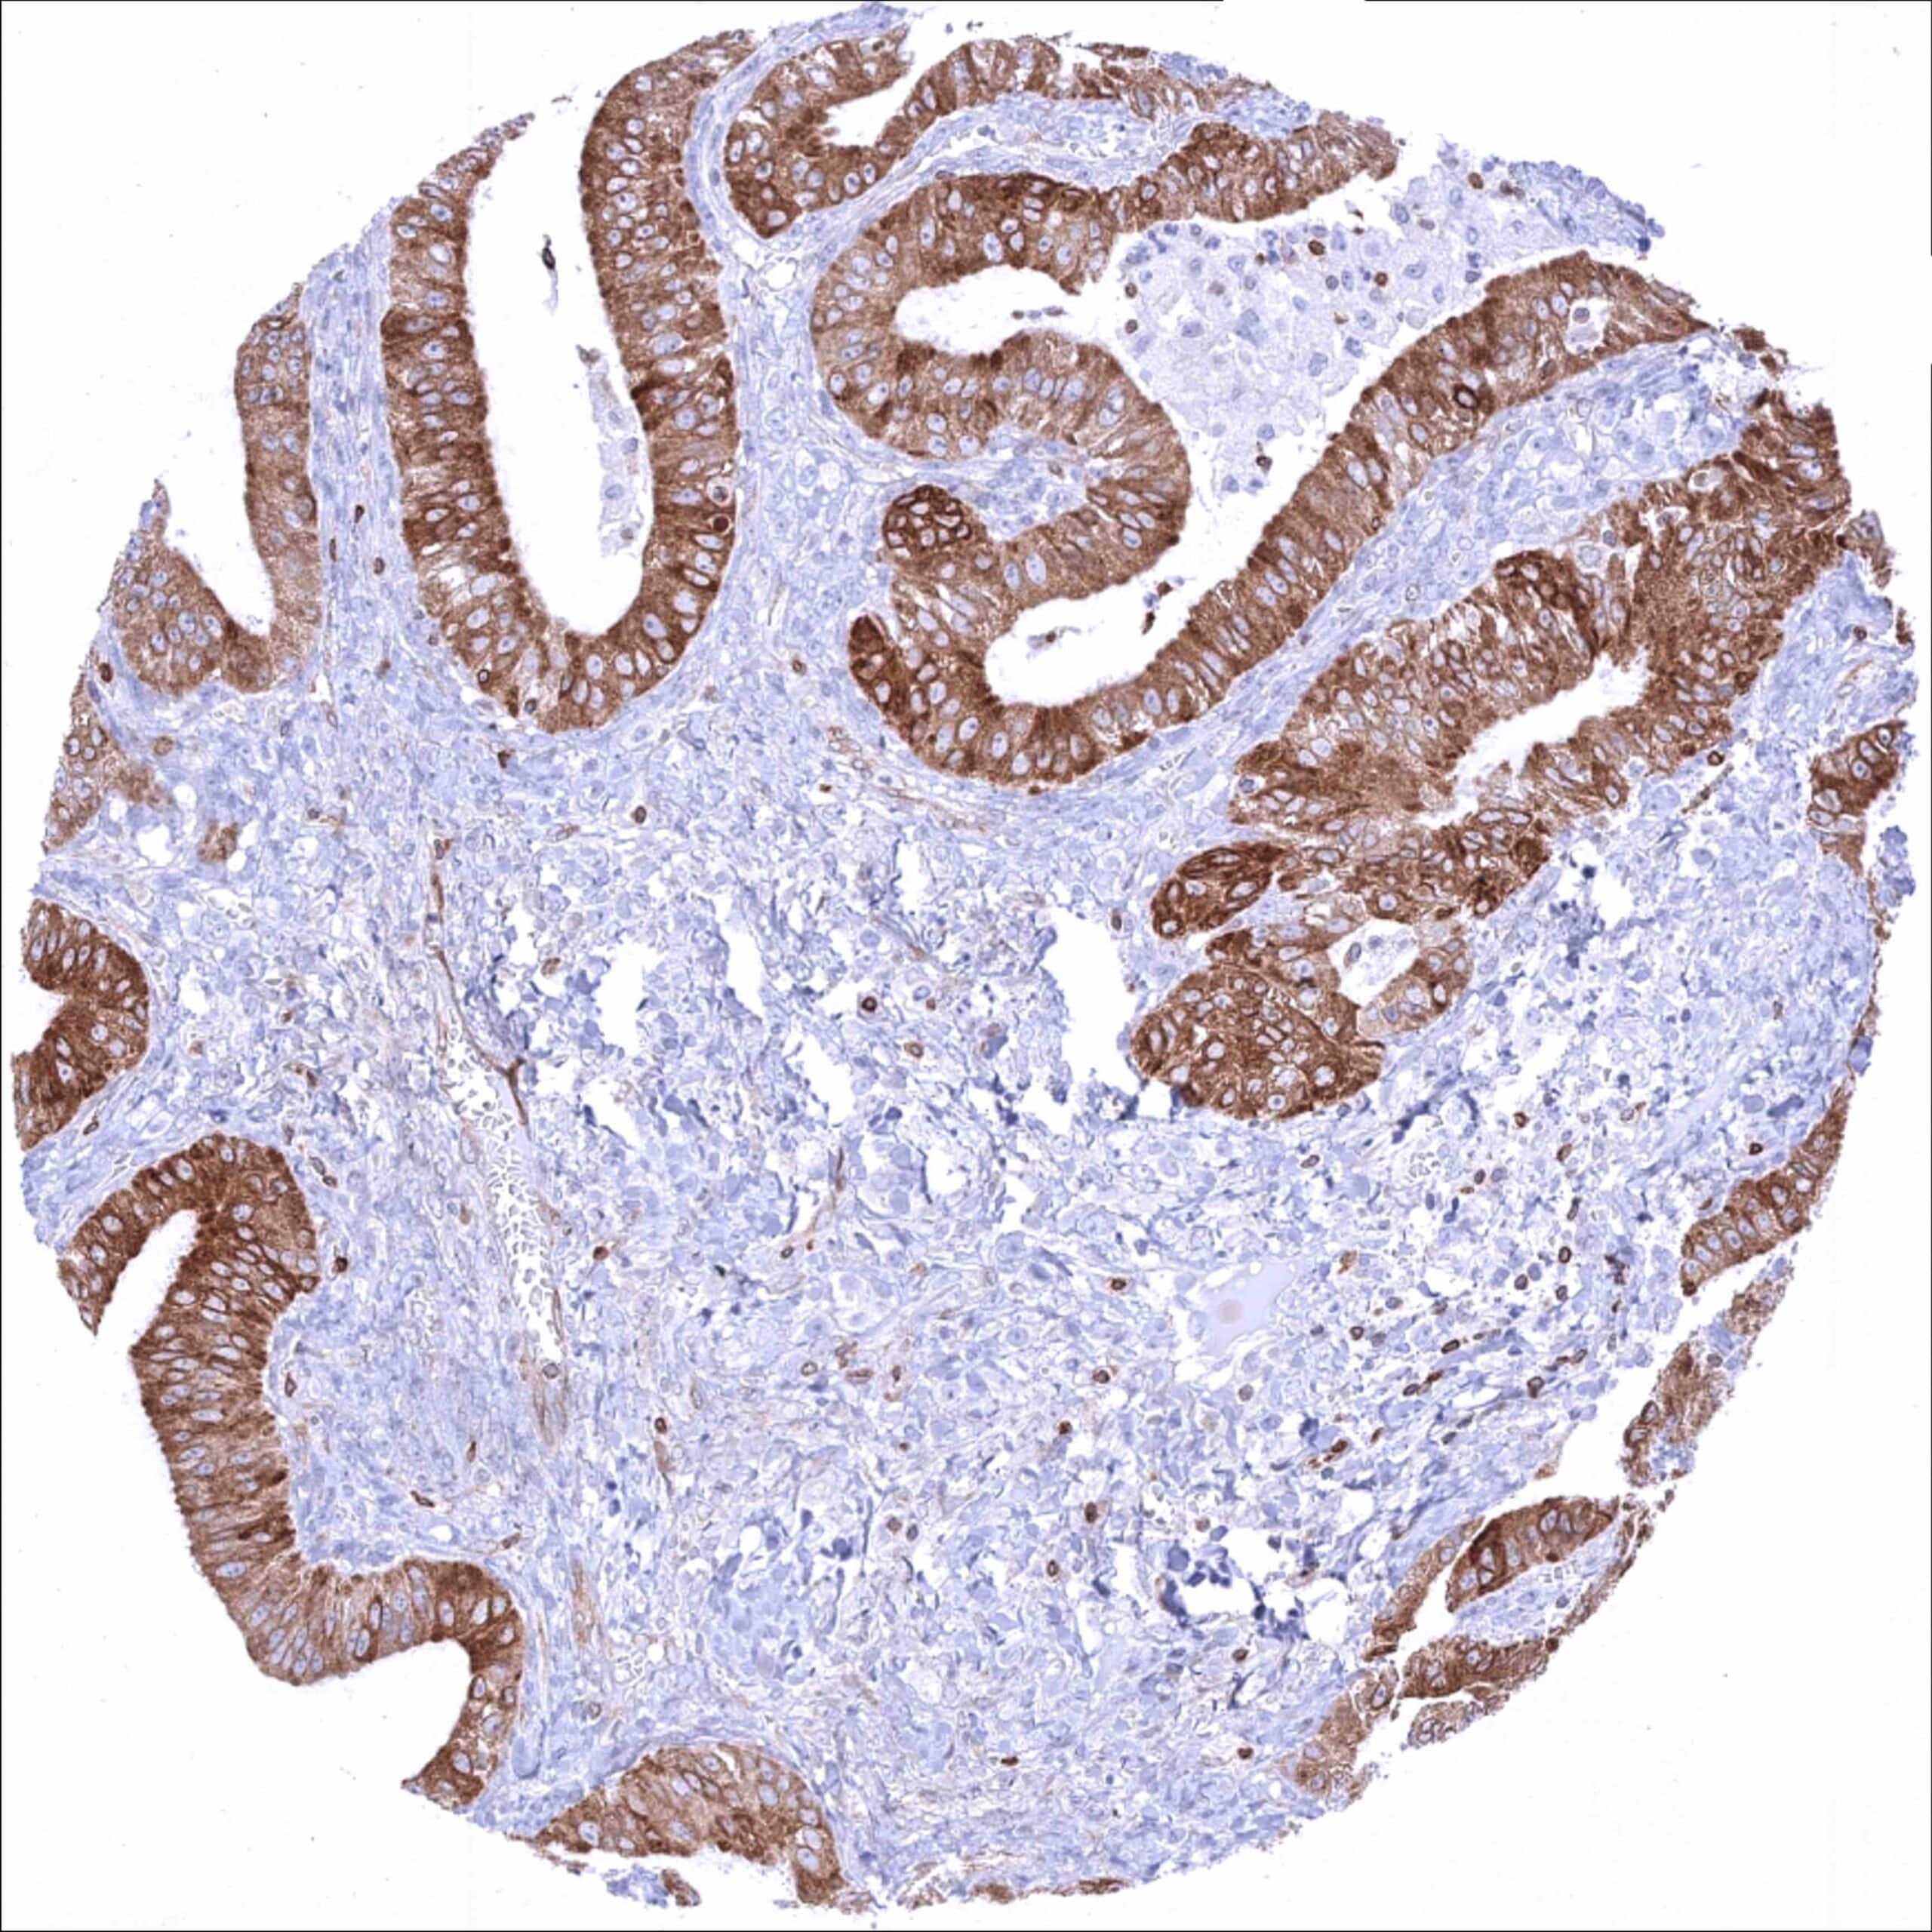

Bcl-2 expression of variable intensity can occur in all types of cancer. It is particularly common in follicular lymphoma.

Comparison of antibodies: True expression of bcl-2 in all cell types with documented bcl-2 immunostaining by MSVA-402M is validated by identical staining patterns obtained by a second, independent commercially available bcl-2 antibody, termed “validation antibody” for all analyzed tissues.